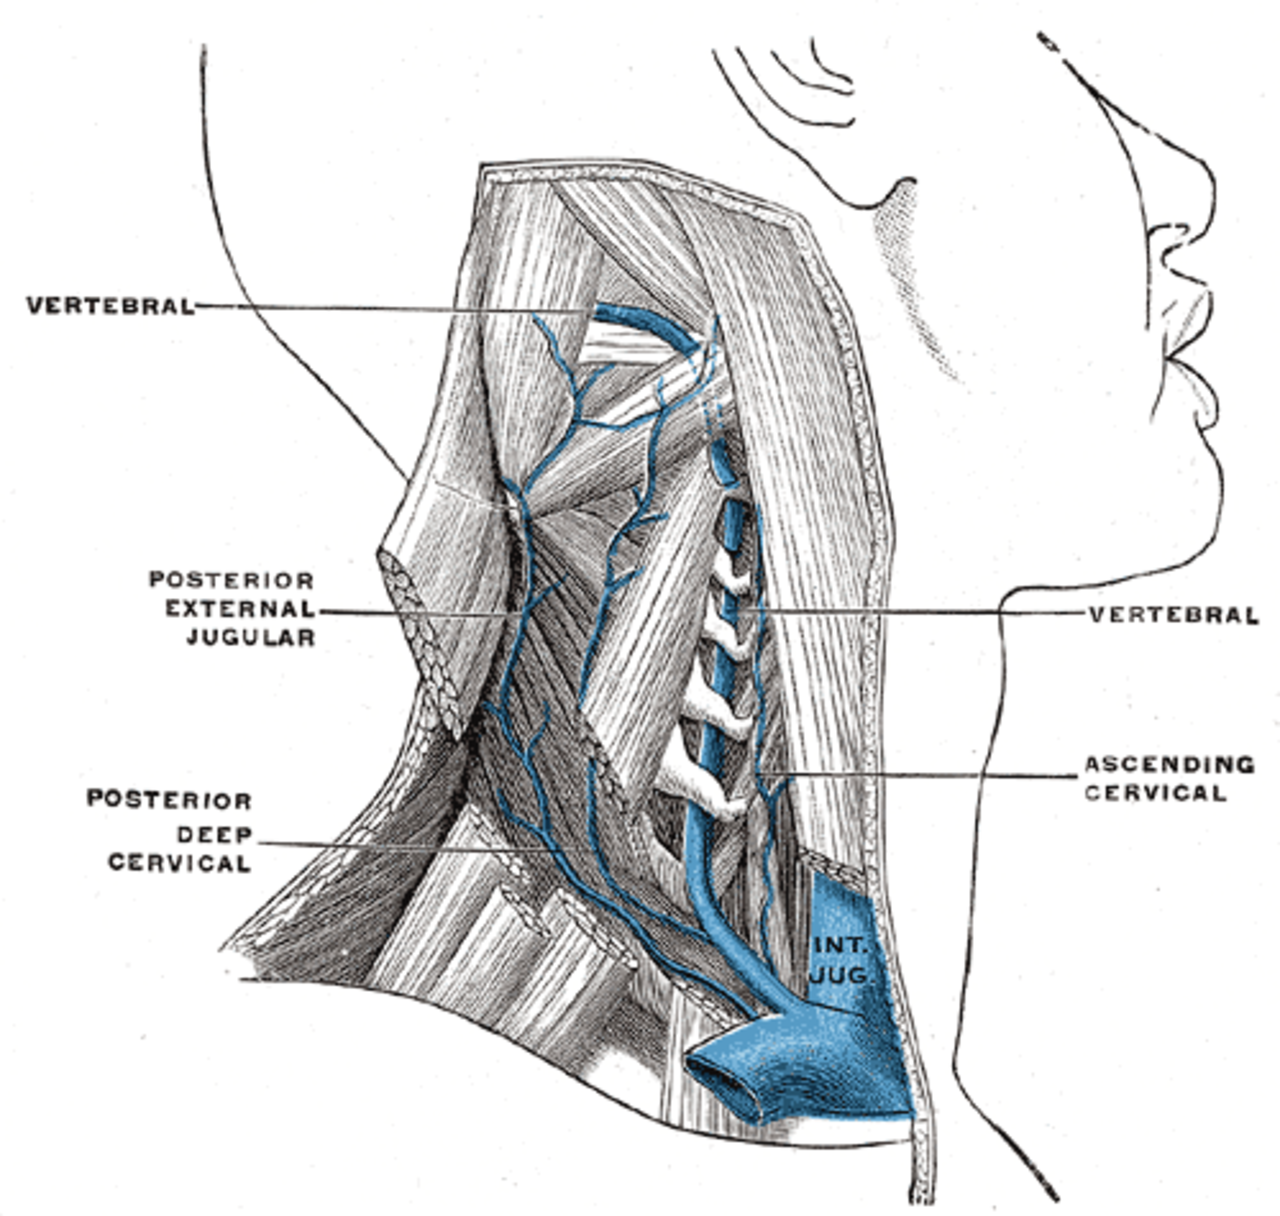

Анатомия внутренней яремной вены: КТ изображения